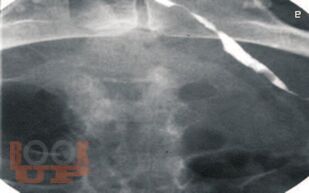

В монографии проанализированы данные литературы и собственные результаты обследования и лечения более 200 пациенток с непроходимостью маточных труб, страдающих бесплодием. Детально описаны методика, рентгенологические и клинические результаты трансцервикальной селективной сальпингографии и реканализации маточных труб под контролем рентгеноскопии. Определена роль чрескатетерных методик в диагностике и лечении трубного бесплодия, их преимущества и недостатки по сравнению с существующими методами коррекции проходимости маточных труб. Сделано заключение о важной роли малоинвазивных трансцервикальных методов в обследовании и лечении пациенток с бесплодием.